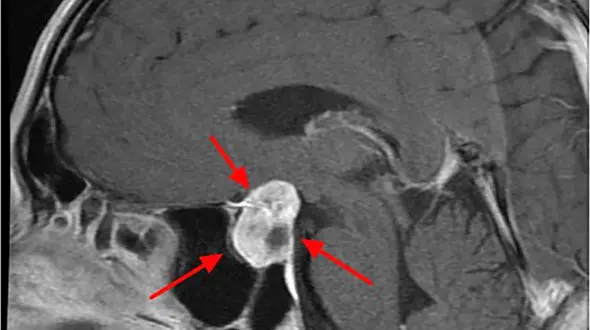

رکنا: چگونگی ایجاد تومور هیپوفیز ، علائم و تشخیص را در این مطلب بخوانید.